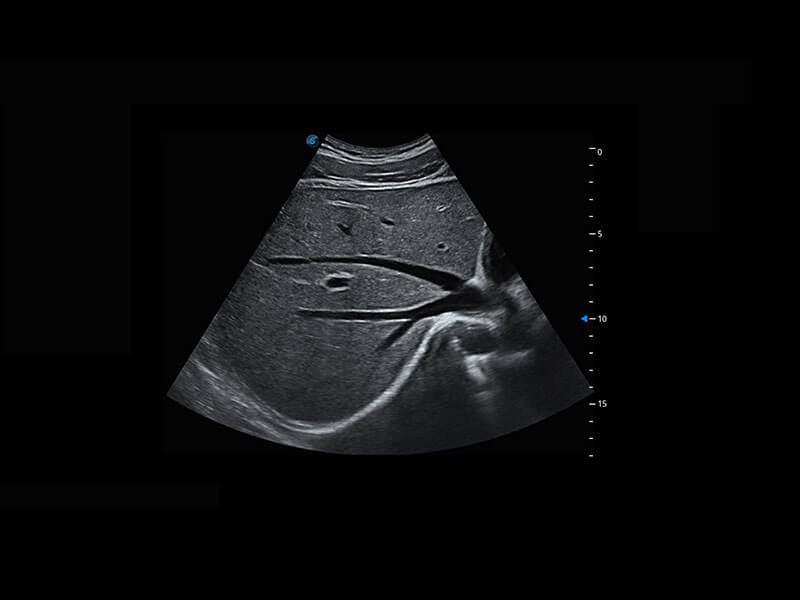

右室双出口